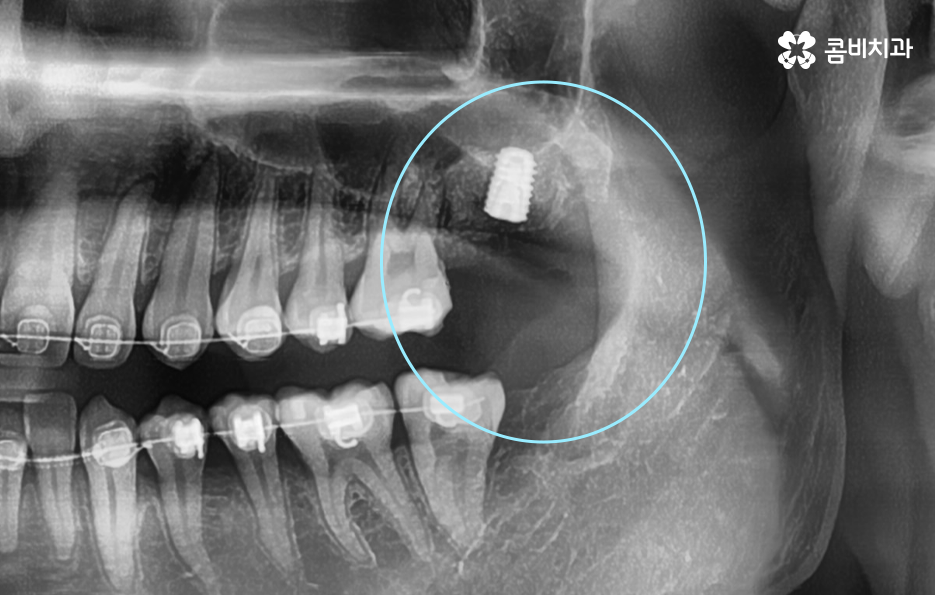

하지만 위 사진에서 보시는 것처럼 치아에서 통증은 못느끼더라도 2차 충치가 발생되어 뒤늦게 치아 내부의 충치에 대해 알게 되면 이미 치아 뿌리까지 충치가 심각하게 진행되어 크라운 재치료가 어려울 정도로 손상이 진행된 경우도 많으며 결국 어금니 발치후 임플란트 치료로 이어질 수 있어요

위 치료 사례의 경우 크라운 내부의 2차 충치로 인해 치아 발치를 진행한 사례이기 때문에 치아 상실의 원인이 충치인 경우에는 잇몸 뼈의 상태 자체는 양호한 경우가 많이 있는데요